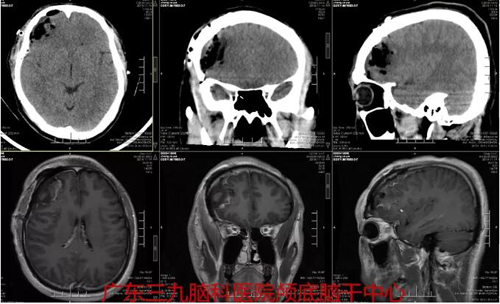

图3:术后CT及磁共振示右侧额叶动静脉畸形切除术改变,结合MRA提示原异常血管团已切除。